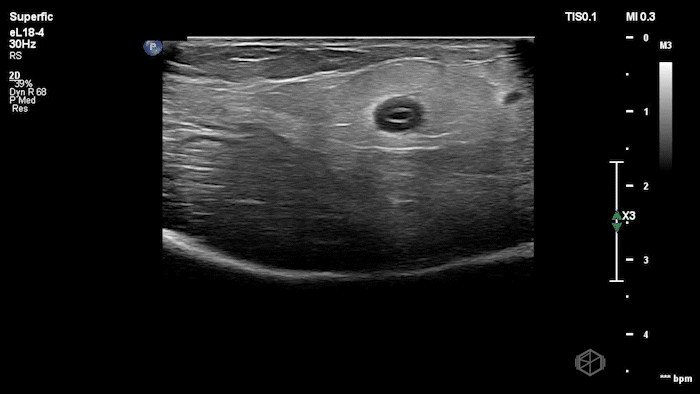

12 - Pediatric patient with right lower quadrant pain only - what is the diagnosis?

Reactive abdominal wall lymph node in the RLQ